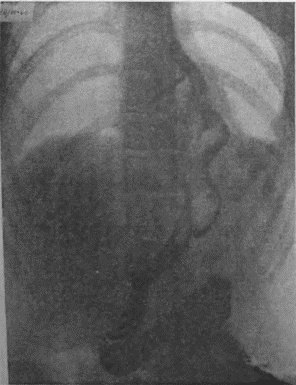

Если при локальном раке кардии и нижнего конца пищевода можно ограничиться все же экономной резекцией фундального отдела, то при более обширном раке или опухолях, захвативших немалую часть верхней трети малой кривизны, иногда возникает вопрос о целесообразности оставления антральной культи взамен тотальной гастрэктомии с трансторакальным соустьем пищевода и тощей кишки. Мотивы для этого могут быть двоякие. Первый и, конечно, главный — это радикальность самой резекции. Вопрос ставится так: да стоит ли сохранять антральный отдел желудка, рискуя, что в нем останутся пока еще невидимые раковые очаги; не вернее ли убрать весь желудок целиком и анастомозировать с тощей кишкой? Не создает ли тотальная гастрэктомия все же большую гарантию от рецидива? Я несколько раз видел отчетливую диссеминацию раковых узелков по передней и задней стенке желудка в радиальных направлениях, исходящую от строго локальной карциномы кардии. Это понуждало резецировать желудок в дистальном направлении весьма широко, оставляя лишь совсем маленькую антральную культю, которую удавалось все же подвести вверх в средостение и там легко анастомозировать с пищеводом тотчас ниже дуги аорты. На прилагаемых рентгенограммах (рис. 95—102) можно видеть, что небольшая культя желудка хорошо подтягивается кверху и прекрасно располагается в заднем средостении на месте иссеченного пищевода. Но каждый раз остается и тревожная мысль, как бы не получилось рецидива именно в этой сохраненной части желудка, поскольку рак проявил склонность к узелковому распространению по самой желудочной стенке. Второе соображение, которое выдвигает мысли о тотальной гастрэктомии, это опасение, что содержимое оставляемой дистальной половины желудка после пересечения обоих блуждающих нервов будет плохо эвакуироваться и тем доставит серьезные неприятности в ближайшем послеоперационном периоде. На моем личном опыте я пока еще не имел такого осложнения, но в нашей клинике однажды наблюдался больной, у которого эвакуация содержимого из оставленной антральной культи была чрезвычайно плохой в течение многих дней после операции. При этом создавалось впечатление, что полная атония оставленной части тела желудка сочетается с выраженным спазмом привратника, который не пропускал принятого бария в двенадцатиперстную кишку. Хотя, в конце концов, все наладилось и больной выписался в хорошем состоянии, однако тревог с ним было очень много. ![]() Рис. 95. ![]() Рис. 96. ![]() Рис. 97. ![]() Рис. 98. ![]() Рис. 99. ![]() Рис. 100. ![]() Рис. 101. ![]() Рис. 102. За сохранение антральной половины желудка и использование ее для прямого анастомоза с пищеводом говорит соблазнительно хорошая васкуляризация этой дистальной половины из сохраненных магистралей: аа. gastro-epiploica dextra et gastrica dextra. Насколько внимательно надо оценивать пригодность фундального отдела после лигирования обеих левых желудочных магистралей и всех vasa gastricae breves при самых высоких, надаортальных соустьях после экстирпаций среднего пищевода, настолько же после резекций проксимальной трети или половины желудка остающаяся дистальная часть превосходно васкуляризируется правыми артериальными магистралями. А это обстоятельство надежнее всего обеспечивает быстрое и прочное сращение по линии желудочно-пищеводного соустья, т. е. наиболее решающий этап всей операции. Мне могут возразить, что, анастомозируя пищевод с тощей кишкой, мы пользуемся органом, не менее богатым по кровоснабжению. Это верно, но поперечник тощей кишки не дает столько простора и пластического материала, сколько его имеется даже на короткой, но широкой антральной культе. Благодаря ширине культи имеется возможность после окончания двухрядного поперечного соустья укрыть дополнительно всю переднюю полуокружность анастомоза, сдвигая и сшивая над ним складки большой и малой кривизны. Прием этот чрезвычайно повышает прочность и герметизм соустья. А риск недостаточности последнего является главной опасностью всех подобных операций. При анастомозах с дистальной половиной желудка мы до сих пор осложнений еще не имели; зато три раза на десяток высоких резекций пищевода и анастомозов с фундальным отделом мы столкнулись с частичной недостаточностью соустья. В двух из этих случаев дело закончилось благополучно, и после вскрытия и дренажа ограниченных эмпием и срочного наложения подвесных энтеростомий для кормления пищевые свищи закрылись самостоятельно и довольно быстро. Но третий больной, врач 52 лет, хорошо перенеся надаортальную резекцию пищевода, постепенно угас, истощаясь из-за чресплеврального свища, получившегося вследствие недостаточности пищеводно-желудочного соустья. Повторяю, не только васкуляризация, но и форма оставляемой желудочной культи предопределяют качество и надежность анастомоза. Поэтому и при наложении раздавливающих гразеровских зажимов на желудок мы стремимся получить не длинную, узкую культю, а широкую, хотя бы за счет ее укорочения. Поднять высоко в средостение короткую культю можно без натяжения; зато ширина ее позволит сделать двойную боковую запашку поверх передней части законченного соустья с пищеводом. Чтобы еще уменьшить натяжение на линии анастомоза, после окончания последнего желудочную культю тщательно укладывают в заднее средостение и пришивают в нескольких местах к краям левой медиастинальной плевры. Наконец, совершенно обязательно пришить желудок к отверстию, оставляемому для него в ушиваемом разрезе диафрагмы. Напомню, что в самом начале операции, как только была вскрыта плевральная полость, n. phrenicus, всегда отчетливо видимый при переходе с перикарда на верхний купол диафрагмы, анестезируется инъекцией новокаина и раздавливается торзионным зажимом. Это создает неподвижность левой половины диафрагмы не только на время вмешательства, но и в течение нескольких месяцев после операции; таким образом, желудочная культя, вшитая в отверстие неподвижной диафрагмы, получает надежную опору и тем дополнительно исключается возможность натяжения в швах анастомоза. |